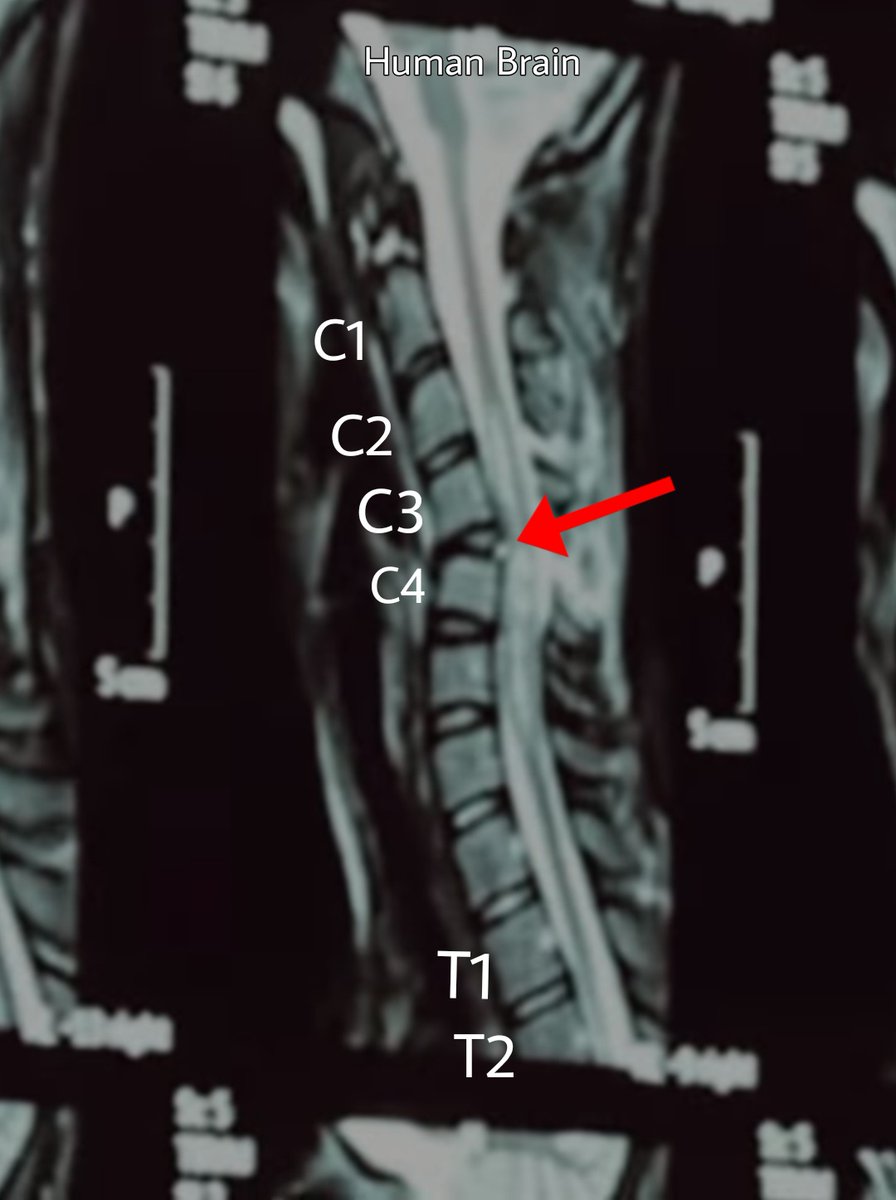

Dia mengalami cedera pada cervical region (tulang leher), C3-C4.

Tulang lehernya udah gk lurus, bengkok. Bantalannya udah pasti keluar, neken spinal cordnya. Ini sedikit gambaran tulang belakang & saraf manusia.

Semua perintah dari otak akan disalurkan melalui saraf ini ke semua bagian tubuh manusia. Pun sebaliknya, mereka juga indra perasa akan mengirim sinyal rasa (sakit dll) melalui saraf untuk dikirm lagi ke otak.